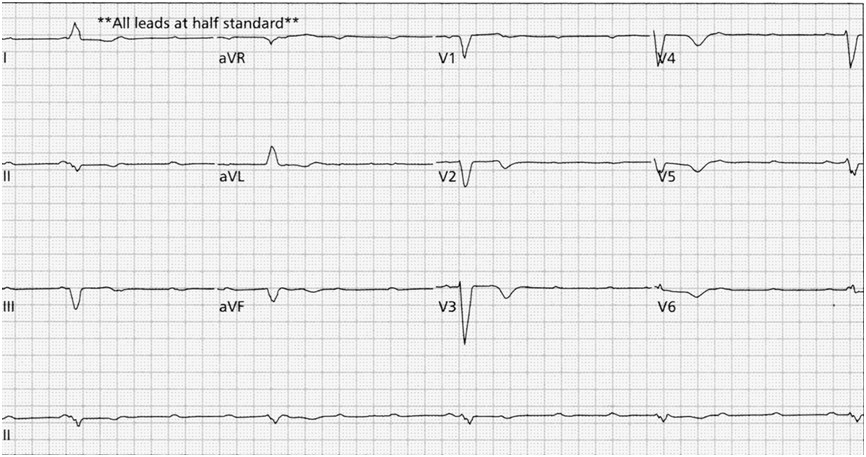

W poniższym zapisie EKG obserwujesz: (Przesuw taśmy 25 mm/s, cecha 10 mm=1 mV)

Mężczyzna nadużywający alkoholu, nieprzytomny podczas robienia EKG. W poniższym zapisie EKG obserwujesz: (Przesuw taśmy 25 mm/s, cecha 10 mm=1 mV)

Mężczyzna lat 68 zgłasza bolesność za mostkiem oraz uczucie zamroczenia. W poniższym zapisie EKG obserwujesz: (Przesuw taśmy 25 mm/s, cecha 10 mm=1 mV)

Pacjent po utracie przytomności. Ciśnienie tętnicze krwi 70/40 mmHg. W poniższym zapisie EKG obserwujesz: (Przesuw taśmy 25 mm/s, cecha 10 mm=1 mV). Twoje postępowanie będzie następujące:

Pacjent z zaburzeniami świadomości. W poniższym zapisie EKG obserwujesz: (Przesuw taśmy 25 mm/s, cecha 10 mm=1 mV)